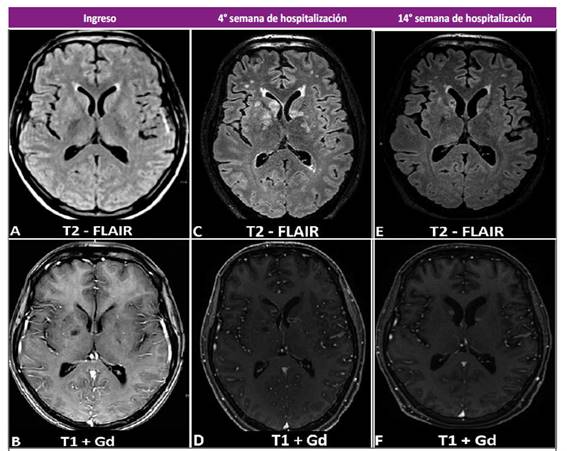

La analítica de ingreso mostró una leucocitosis con neutrofilia y linfopenia relativa y absoluta, resto de los exámenes dentro de parámetros normales (Tabla 1). En la resonancia magnética (RM) cerebral que trajo consigo mostró una lesión en núcleos basales izquierdos sugerente de un infarto cerebral debido a una probable vasculitis infecciosa (Figura 1). Se realizó una punción lumbar obteniéndose líquido cefalorraquídeo (LCR) con características inflamatoria crónica, consumo de glucosa, tinta china positiva, y un cultivo que posteriormente resultó positivo para Cryptococcus spp (Tabla 1). La tomografía de tórax mostró lesiones sugerentes de criptococosis pulmonar (Figura 2). Se diagnosticó criptococosis meníngea confirmada y pulmonar probable, iniciándose tratamiento con anfotericina B desoxicolato (AmBd) y fluconazol vía endovenoso.

Figura 1 Resonancia magnética cerebral en secuencia FLAIR y T1+Gd. (A-B) Se observa discreta dilatación de los espacios perivasculares, e hipointensidades irregulares en el territorio profundo de ambas arterias cerebrales medias. (C-D) A nivel de ganglios basales se aprecia múltiples imágenes nodulares hiperintensas captadoras de contraste con edema perilesional. (E-F) Disminución del número de lesiones anteriormente descritas, así como de la captación de contraste y edema perilesional.

Tras una evolución clínica y laboratorial favorable (cultivo control de hongos en LCR negativo), y por dificultades económicas para conseguir la AmBd, se suspendió dicho fármaco en la tercera semana de tratamiento, continuándose únicamente con fluconazol. Días posteriores el paciente empeoró clínicamente, se realizó un nuevo cultivo de hongos en LCR, observándose nuevamente crecimiento de levaduras (Tabla 1). Igualmente, se indicó una RM cerebral mostrando nuevas lesiones en núcleos basales, cerebelo e ínsula sugerentes de criptococosis parenquimal (Figura 1).

Se decidió reiniciar tratamiento con AmBd asociado a fluconazol, y corticoides para el manejo del edema cerebral. Recibiendo una dosis total de AmBd de 2,3 gramos, administrados en un esquema individualizado (infusión interdiaria durante 8 semanas) para minimizar efectos adversos de la medicación. Con evolución clínica, laboratorial (Tabla 1) e imagenológica (Figura 1) favorable, continuando solo con fluconazol vía oral, sin recaídas hasta la publicación del presente reporte.